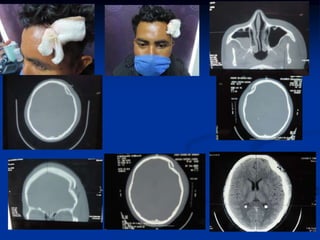

Niño con TCE , fallecio

Caso clínico del dia 31 de dic 2015

Niña con TCE

 Niña de 2.5 años de edad

 Vehiculo en mov

 Llega a hosp privado

 La quieren pasar a uci y

multi-especialistas

 Acepte el caso y se

atendió en la cruz roja

 Estuvo 5 días y efgreso

sin cirugía

TCE

FRACTURA